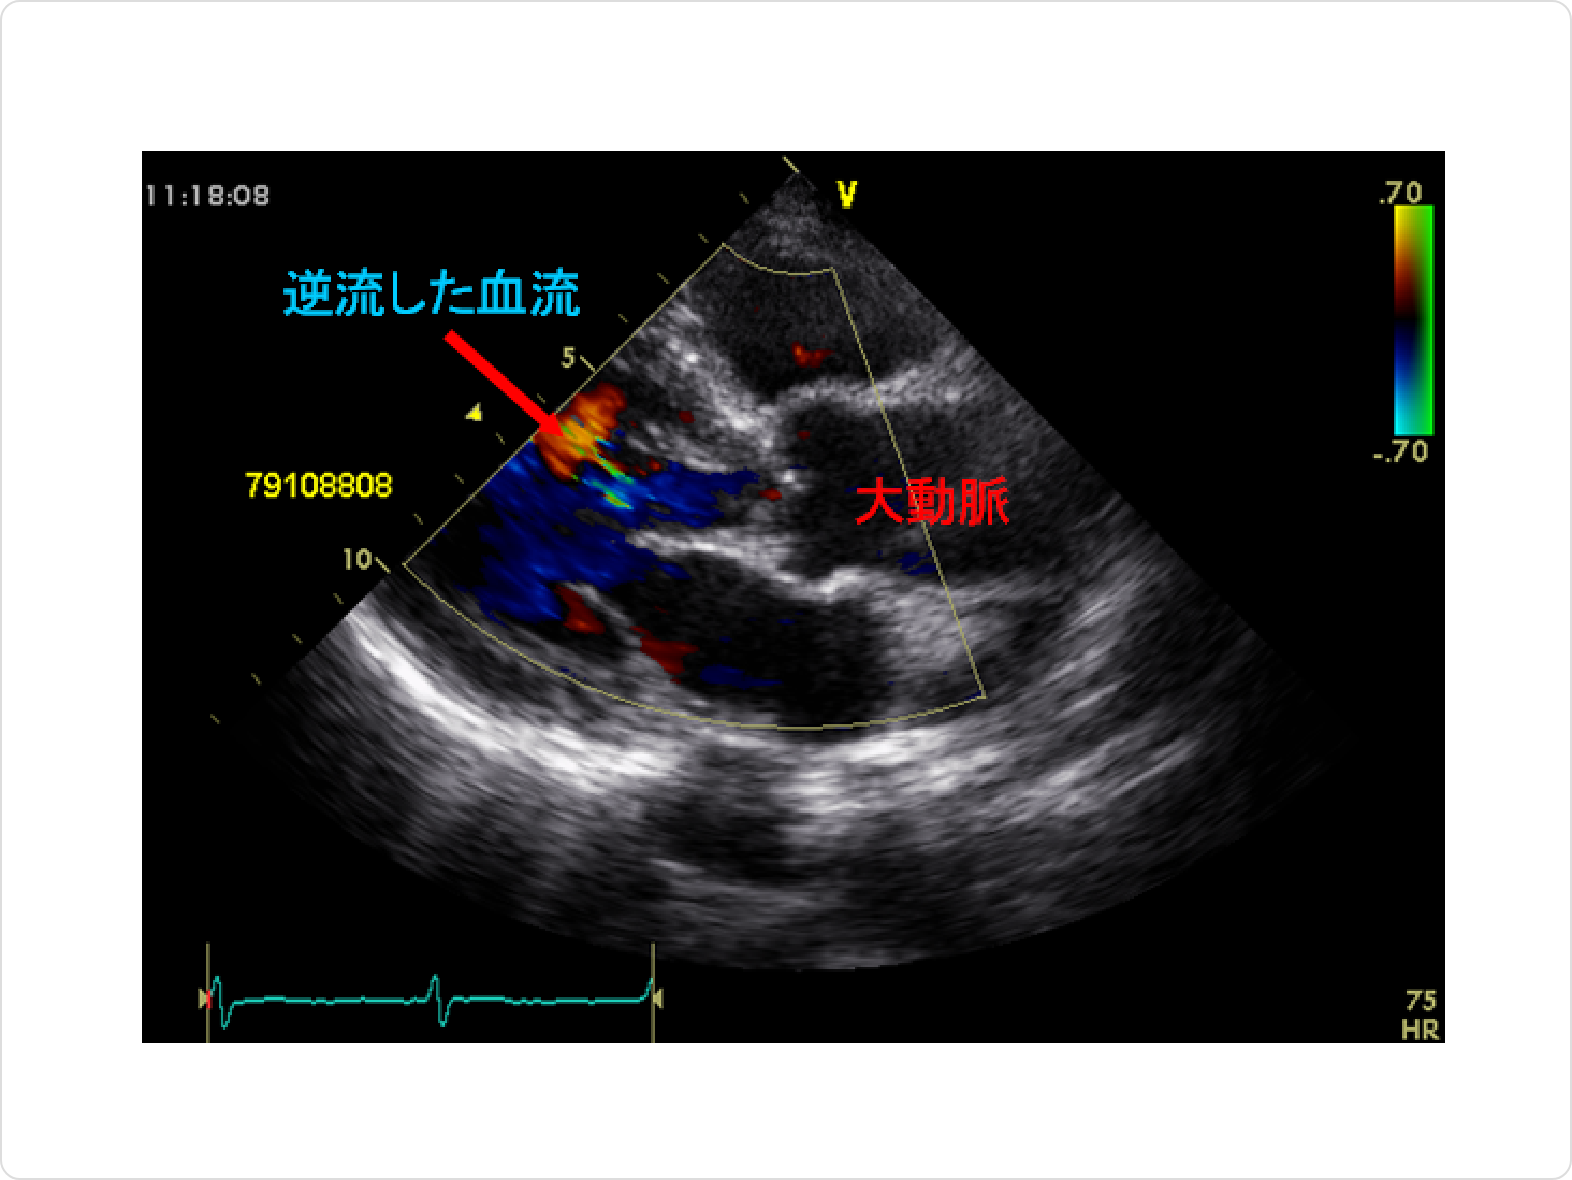

心臓超音波(心エコー)

心臓超音波(心エコー)は、簡便で安全な検査です。心臓の働き、逆流の程度などが短時間でわかります。大動脈弁閉鎖不全のある方は、定期的に行うべき検査です。